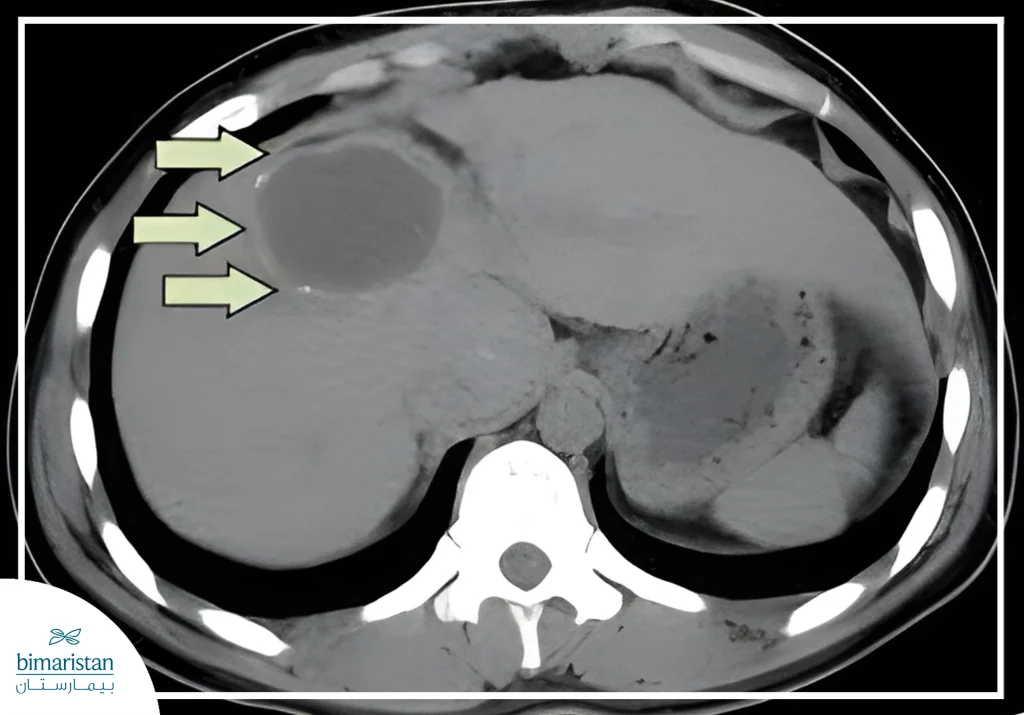

- التصوير المقطعي المحوسب:

- دقة تشخيصية عالية تصل إلى 95–98% حيث يحدد عدد الكيسات وحجمها وموقعها بدقة ويقيم ارتباطات الكيسة بالأوعية الدموية والطرق الصفراوية ويميزها عن الخراجات القيحية والأكياس الكبدية الأخرى